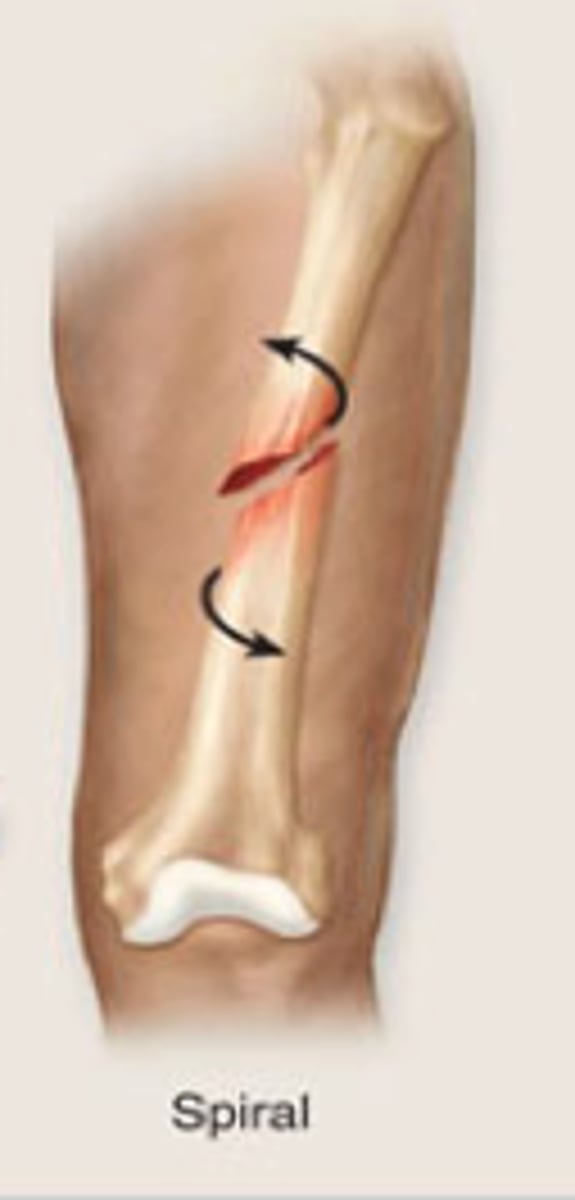

spiral

a fracture in which the bone has been twisted apart